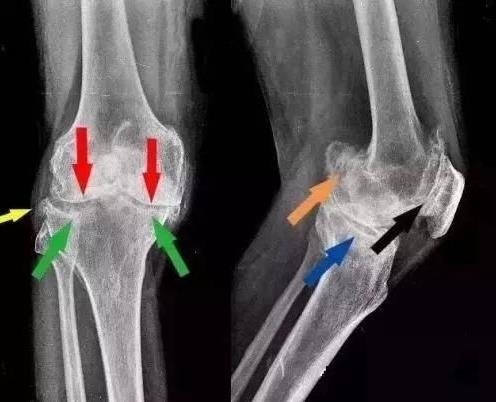

骨质增生,又称骨刺,是困扰中老年人的一种常见的骨科疾病,严重影响人们的生活和工作,得了骨增生那怎么治疗呢?

骨折和外伤也是成骨发生的重要诱因,两者都可导致创伤性关节炎,尤其是骨折复位不全,容易造成关节软骨表面不平,从而发生成骨。因此,一旦出现上述问题,就要及时就医,及时诊断和治疗创伤性关节炎,避免关节发生骨质发生。另外,对于骨质增生的患者,要及时就医,防止病情恶化。